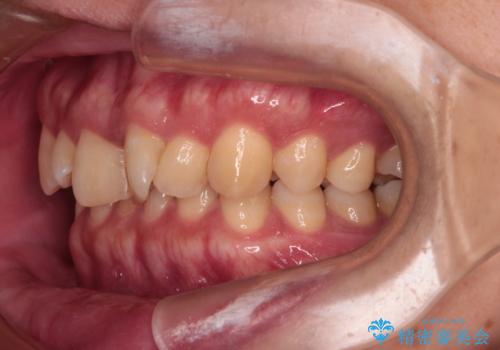

- 前歯のデコボコと深い咬み合わせを気にして来院された患者様です。

骨格的に上顎骨がやや前方にあり、それが原因で下顎前歯が隠れるほどのディープバイトになっている状態でした。

上顎歯列を遠心移動させたことで、前歯の叢生が解消されても前歯が前突することなく、左右ともに理想的な咬み合わせを達成することができました。